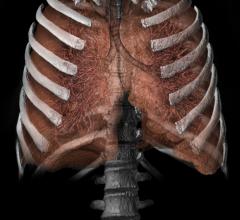

Feature | Dave Fornell

The Society of Cardiovascular Computed Tomography (SCCT) annual meeting July 10-13 in San Diego covered the latest CT…